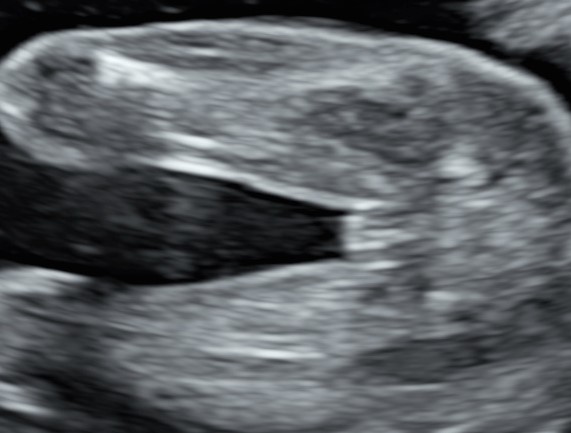

L’indagine è una visione sistematica dalla testa ai piedi del bambino, le sue misure con il calcolo del peso e la valutazione del suo benessere basandosi sui movimenti, Il liquido amniotico ed alcuni parametri vascolari investigati con la doppler flussimetria, come il dotto venoso.

E sempre sul lato materno, in questa ecografia ricontrolliamo la lunghezza della cervice uterina per valutare il rischio di parto prematuro.